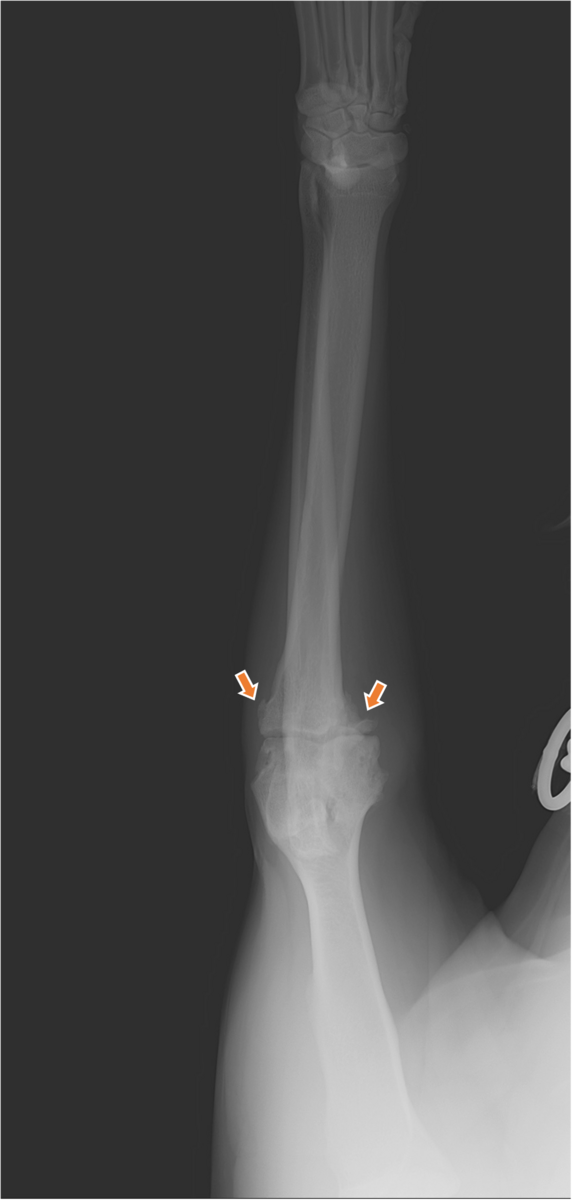

また、レントゲン検査では、下の写真のように、肘関節の周囲に骨棘形成を確認(矢印)し、関節炎が起こっている可能性がありました。